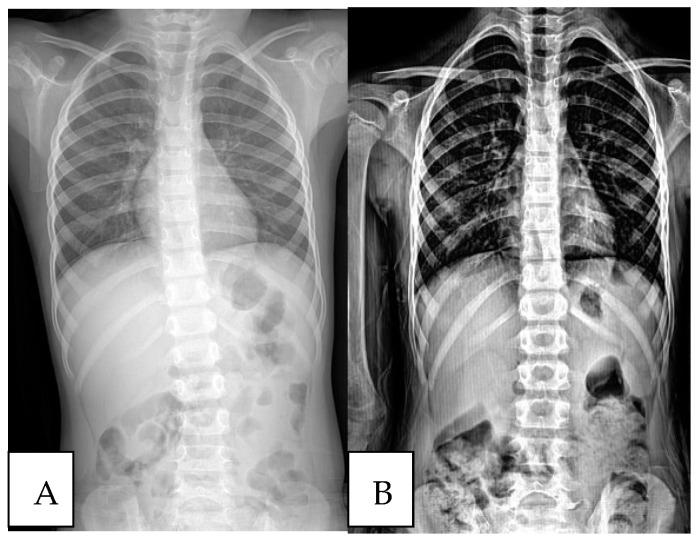

Employing a retrospective cohort design, this study gathered data from patients who underwent adenoidectomy, including those with scoliosis, between January 2017 and March 2023. Initial and follow-up evaluations involved clinical and radiological assessments, notably measuring the Cobb angle to quantify spinal curvature.

This study enrolled 218 patients under 10 years old. Among them, 18 exhibited Cobb angles of 10° or more, with a mean Cobb angle of 12.8°. In the follow-up evaluation, 83% of patients with initial Cobb angles of 10° or more were reached out to, along with 84.6% of those with Cobb angles below 10°. The postoperative follow-up revealed a notable decrease in Cobb angles for most patients, particularly those with an initial Cobb angle exceeding 10°.

本研究纳入了218名10岁以下的患者。其中,18名患者的Cobb角为10°或更大,平均Cobb角为12.8°。在随访评估中,初始Cobb角为10°或更大的患者中有83%被随访,Cobb角低于10°的患者中有84.6%被随访。术后随访显示,大多数患者的Cobb角显著减小,尤其是初始Cobb角超过10°的患者。